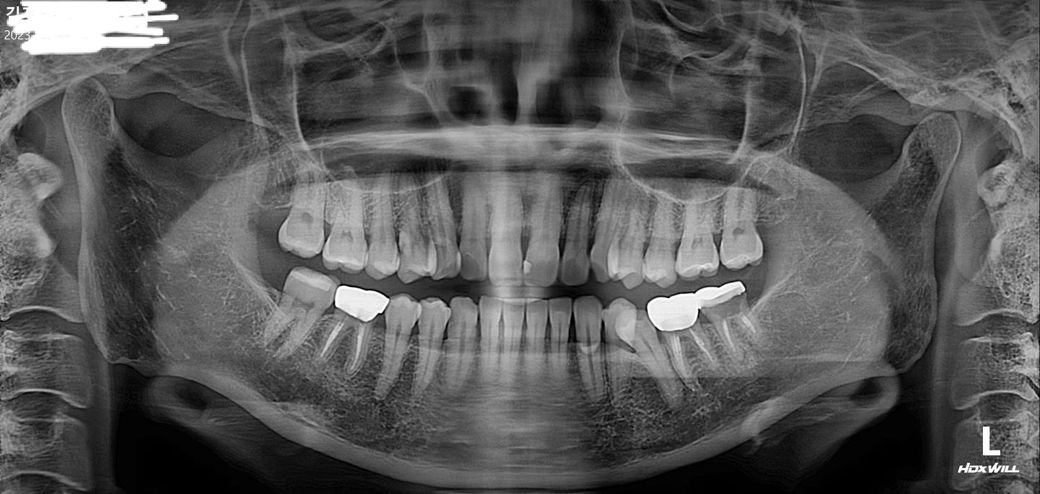

크라운치료후 파노라마사진상 비어보이는부분

신경치료후 크라운했습니다. 37번 이구요..파노라마사진으로 보니 안에가 비어있는듯 보여요. 레진코어로 메꾸어 있지 않은것처럼 보이는데 잘못된 치료인가요?

x-ray 나타나지 않는 치과재료로 메울 경우 비어 있는 것 처럼 보이지만 실제로는 다 메워진 것이니 걱정 안해도 됩니다.

방사선 불투과상이 아니라 투과상이면 저렇게 나타납니다. 해당부분은 걱정안하셔도 됩니다.

레진코어를 햇어도 아래쪽으로 치아를 보호하는 약재로 덮은경우에는 저렇게 엑스레이 선상에 안보이는경우가 있습니다.

치과용 재료 중에서는 방사선 투과성이 있는 재료로 충전을 했얼 경우 방사선상으로 비어 보이는 경우도 있습니다.

또한 내부가 빈 경우에도 어둡게 보일 수 있기 때문에 정확한 확인을 위해서는 치과에서 검사를 받아 보는 것이 좋습니다